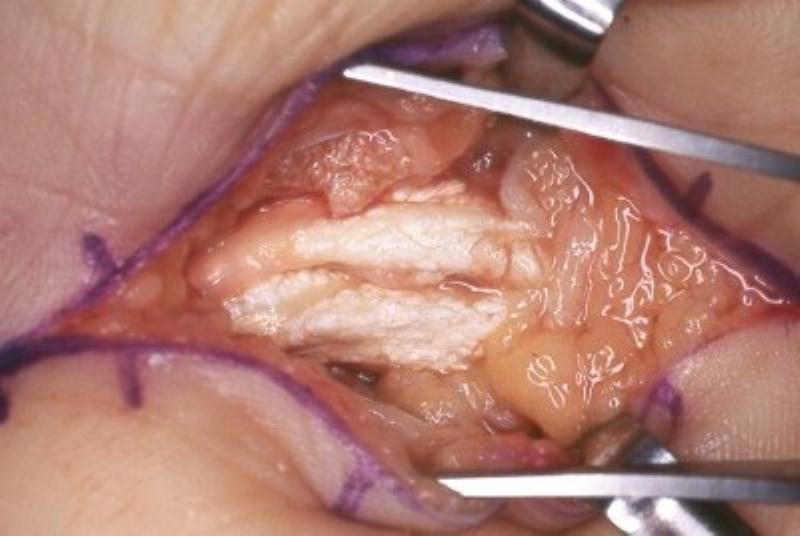

Clinical Example: Gout